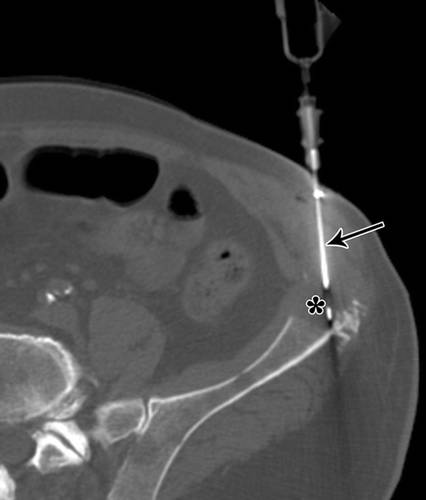

应避免穿过股直肌的前路(图9))。这些伸肌的切除(特别是股直肌)在保留肢体的手术中提供了不理想的结果。如果病变与股血管密切相连,则采用内侧入路是因为内侧切口有利于血管的探查。外侧入路通常更符合人体工程学的可行性,避免了内侧神经血管结构,尤其是如果股外侧肌无血管受累时(图10A,10B)。在大腿远端,髌上凹陷可能向近端延伸一个不同的距离,应该与其余的膝关节一起避免。对于内侧入路,我们可以提升腿部进行活检或弯曲,从外侧旋转对侧髋关节,以便于进入大腿内侧。

![]()

9 -大腿轴向图

10A - 58岁男性转移性腺癌MRI冠状位。

10B - 58岁男性转移性腺癌CT引导下穿刺。